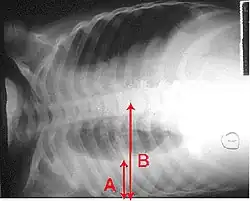

Billeder

Et røntgenbillede af thorax (brystkassen) bruges ofte til diagnoser.[10] Patienter med milde tilfælde skal kun røntgenfotograferes, hvis der er mulighed for komplikationer, eller patienten ikke har reageret på behandlingen, eller hvis årsagen er ukendt.[10][38] Hvis patienten er så syg, at man må indlægge, anbefales det at tage røntgenbilleder.[38] Billedet viser ikke altid sygdommens sværhedsgrad og kan ikke skelne mellem bakterie- og virusinfektion.[10]

Røntgenbilleder af lungebetændelse kan vise lobær pneumoni, bronkopneumoni (også kendt som betændelse i en lungeklap eller pletvis udbredt lungebetændelse) og interstitiel pneumoni.[41] Bakteriel lungebetændelse erhvervet uden for sygehus viser sig typisk ved lungekonsolidering af et lungesegment, og det kaldes lobær eller primær pneumoni.[20] Men andre mønstre kan vise sig ved andre typer lungebetændelse. Ved aspirationspneumoni kan der være uklare områder nederst i begge lunger og i højre side.[20][20] Hvis lungebetændelsen er viral, kan røntgenbilleder se normale ud, eller de kan vise hyperinflation, pletter i begge sider eller de kan ligne billeder af bakterielle lungebetændelser med lungekonsolidering.[20] Røntgenbilleder viser måske ikke noget tidligt i forløbet, især, hvis patienten er dehydreret, eller de kan være svære at tyde, hvis patienten er overvægtig eller tidligere har haft lungesygdomme.[11] En CT-skanning kan give yderligere oplysninger, hvis det kræves.[20]